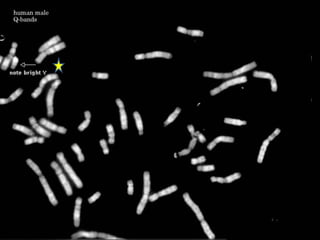

Q banding

• Used especially for Y chromosome

abnormalities or mosaicism

• Similar pattern to G banding

– But can detect polymorphisms

• Needs fluorescent microscope